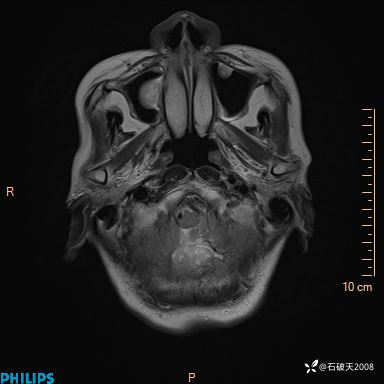

书上说这个肿瘤发生在幕下仅4.09%,你会想到它吗?(病理已公布)

T1